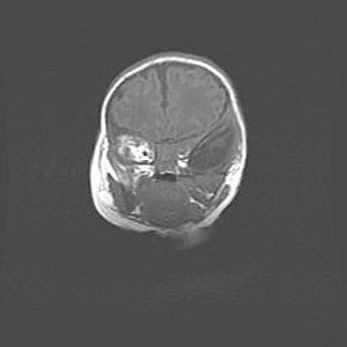

Подострая гематома правой гемисферы мозжечка.

Наружная гидроцефалия.

Возраст: 15 дней

Вес: 3100 г

Пол: женский

Окружность головы: 37 см

Срок гестации: 35-36 недель

При открытой наружной форме гидроцефалии у новорожденных расширяются и переполняются субарахноидные пространства.

Кровоизлияния в мозжечок имеют две клинико-анатомические формы: полушарные гематомы и кровоизлияния в червь.

К появлению этой патологии может привести: повреждения головного мозга, возникающие в результате асфиксии и гипоксии плода при беременности, или травмы во время родов. Редко гематома мозжечка может быть результатом первичной коагулопатии и сосудистой мальформации, диссеминированном внутрисосудистом свертывании, изоиммунной тромбоцитопении.